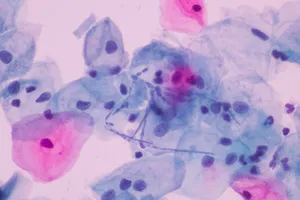

- 자궁경부암의 경우: HPV 감염이 원인인 경우가 많아, 조기 검진(세포진 검사나 HPV 검사)을 통해 암으로 발전하기 전 단계(이형성증)를 발견하고 치료할 수 있습니다. 이는 암 자체를 예방하는 효과가 있습니다.

2. 정기적인 자궁경부암 검진

- 20세 이상 여성은 2년마다 자궁경부세포검사를 받는 것이 좋습니다.

- 30세 이상 여성은 HPV 검사를 추가로 받는 것이 좋습니다.